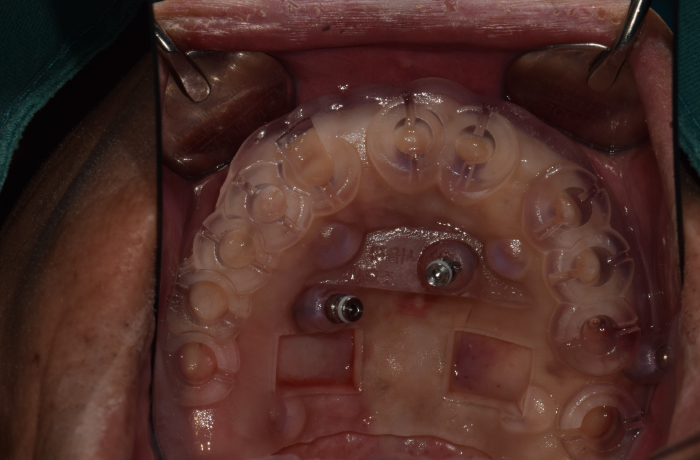

즉시 식립 임플란트 전후 사례

• 식립 전

식립 후